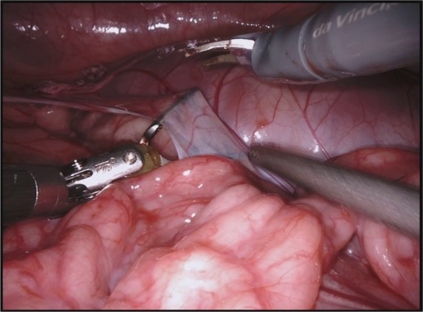

Visual question answering (VQA) in surgery is largely unexplored. Expert surgeons are scarce and are often overloaded with clinical and academic workloads. This overload often limits their time answering questionnaires from patients, medical students or junior residents related to surgical procedures. At times, students and junior residents also refrain from asking too many questions during classes to reduce disruption. While computer-aided simulators and recording of past surgical procedures have been made available for them to observe and improve their skills, they still hugely rely on medical experts to answer their questions. Having a Surgical-VQA system as a reliable 'second opinion' could act as a backup and ease the load on the medical experts in answering these questions. The lack of annotated medical data and the presence of domain-specific terms has limited the exploration of VQA for surgical procedures. In this work, we design a Surgical-VQA task that answers questionnaires on surgical procedures based on the surgical scene. Extending the MICCAI endoscopic vision challenge 2018 dataset and workflow recognition dataset further, we introduce two Surgical-VQA datasets with classification and sentence-based answers. To perform Surgical-VQA, we employ vision-text transformers models. We further introduce a residual MLP-based VisualBert encoder model that enforces interaction between visual and text tokens, improving performance in classification-based answering. Furthermore, we study the influence of the number of input image patches and temporal visual features on the model performance in both classification and sentence-based answering.